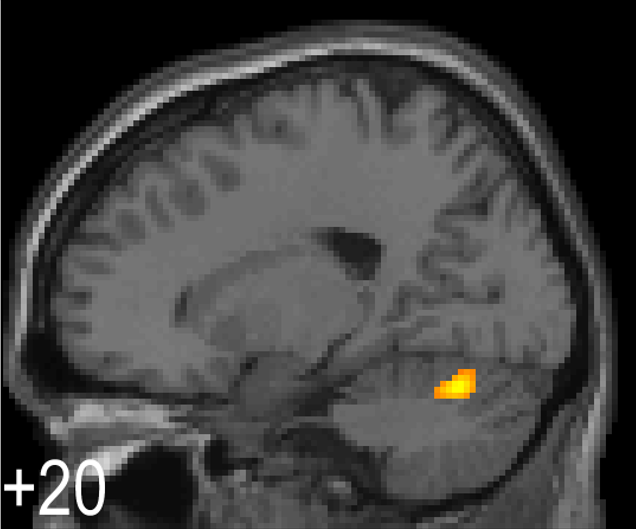

小脳は運動機能や言語機能、眼球運動、平衡機能と密接に関係していることは古くから知られています。また、運動遂行時においては運動の実行と運動肢からのフィードバックの差(誤差)の修正に小脳は重要な役割を果たすことがわかっています。一方、近年の脳機能イメージング技術の発展に伴い、表在感覚である触覚刺激によっても小脳が活動することがわかってきました。しかし、この小脳の活動は、単に擦られる強さに応じて増減するのか、皮膚上を物体が動く方向や速度、擦られる粗さや滑らかさに関係しているのか、より高次な"擦られ心地"のような認知機能と関係しているのかなど、その役割は全くわかっていません。本研究では、脳機能イメージング手法<Functional MRI(図1),Voxel based morphometry (VBM, 図2),MR spectroscopy (MRS, 図3), Functional connectivity解析(図4)など>を駆使して、大脳および小脳の構造解析・機能解析を詳細に行い、皮膚を擦られた際の情報処理に係わる「小脳の役割」を探求していきます。さらに、触覚刺激の物理特性と官能検査による心理特性もあわせて解析することにより、単に表在感覚情報処理にかかわる小脳の役割を解明するだけでなく、アスリートの"研ぎ澄まされた感覚"の神経基盤を解明したいと考えています。

【図1】触圧覚刺激時における小脳の活動